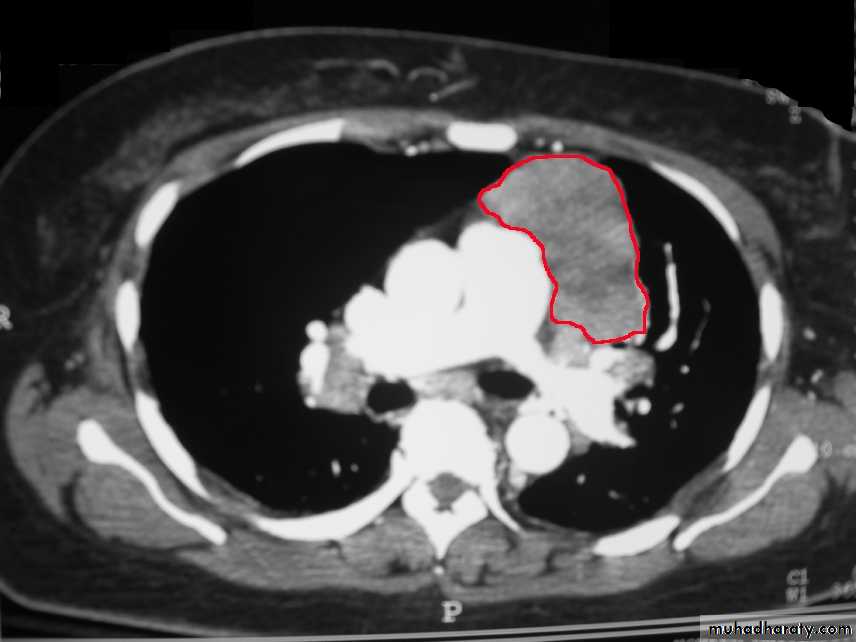

Mediastinal masses are recognized on frontal radiographs by the presence of a soft tissue density that causes obliteration or displacement of the mediastinal contours or interfaces. The lung -mass interface typically is well defined laterally, where it is convex with the adjacent lung, and it creates obtuse angles with the lung at its superior and inferior margins. This latter characteristic is diagnostic of an extrapulmonary lesion, whether intramediastinal or pleural. Lateral displacement of the trachea or heart may be seen with large mediastinal masses, sometimes first recognized by displacement of an indwelling endotracheal tube, nasogastric tube, or intravascular catheter.

Frontal and lateral chest radiographs usually localize a mediastinal mass to a structure within the anterior, middle, or posterior mediastinal compartments. For instance, if the contours of a lesion are outlined by air and seen above the clavicles, then the lesion must be in the posterior mediastinum. Conversely, if the contours of a lesion are lost at the thoracic inlet level, it must be anterior

Basically four types of lesions tend to occur in the anterior mediastinum: substernal thyroid gland, thymic lesions, germ cell, and lymphoma. Students can remember most of the anterior mediastinal lesions by using the four Ts. This stands for thymoma, thyroid lesions, teratoma , and T-cell lymphomas.